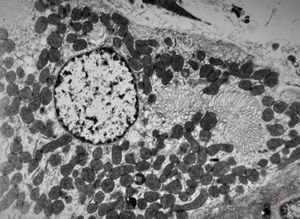

normal mucosa - stomach - parietal cell